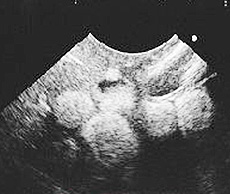

3診断

- 卵殻形成前の卵胞が超音波検査で大量に確認される

超音波検査で卵胞多数